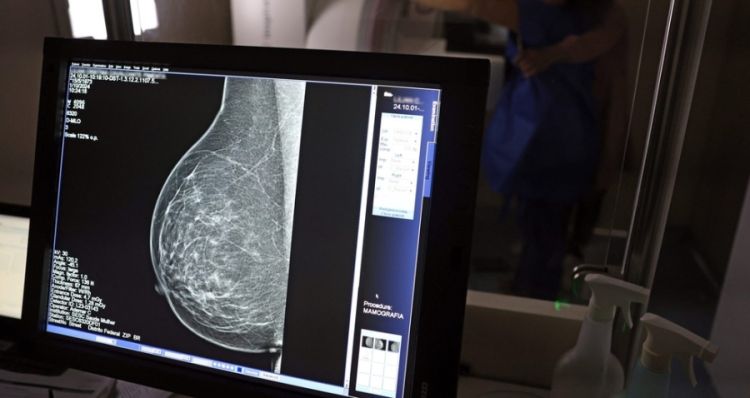

A inteligência artificial pode ser utilizada para prever o risco de doenças cardiovasculares em mulheres a partir de análises de mamografias.

Segundo a pesquisa, a IA consegue avaliar o acúmulo de depósitos de cálcio nas artérias da mama a partir dos exames de raio-x, muito utilizados para o rastreamento de câncer.

A calcificação arterial das mamas costuma ser identificada em mamografias de rotina e não tem relação com tumores. Mas, diversos estudos mostram a associação da calcificação com fatores de risco cardiovascular e futuro desenvolvimento de doenças cardíacas.

A técnica pode ser uma importante aliada no diagnóstico precoce de problemas cardiovasculares em mulheres, a partir de um exame que já é feito rotineiramente com outro propósito.